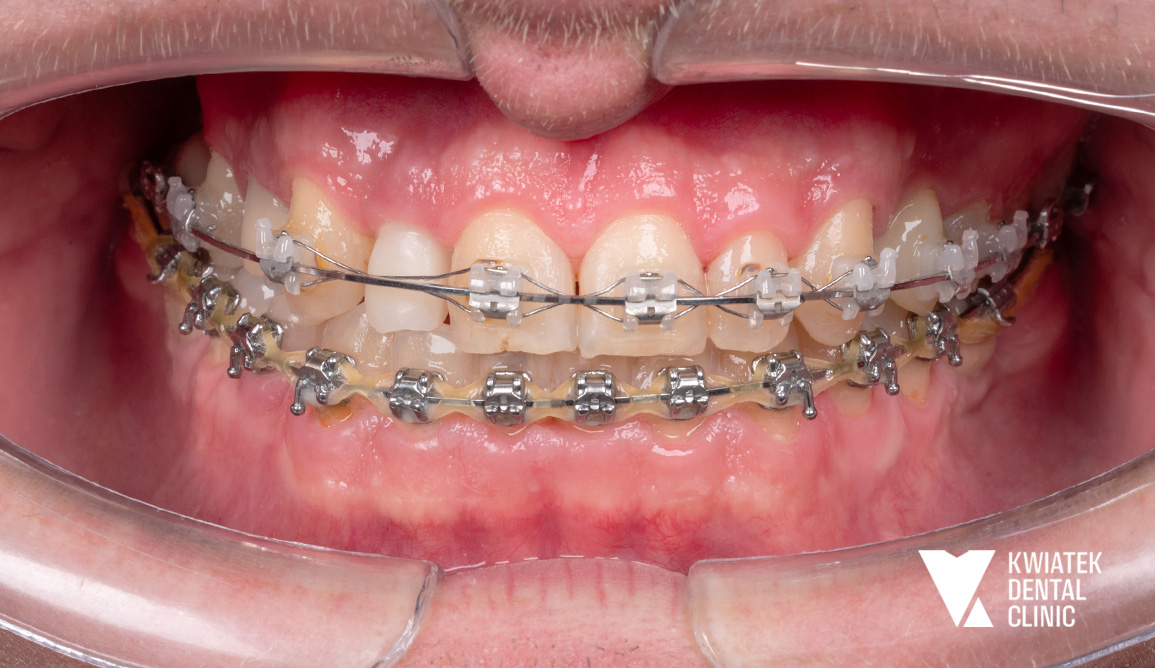

Po odbudowie fundamentów rozpoczęto leczenie ortodontyczne, którego celem była korekta ustawienia zębów i przygotowanie optymalnych warunków dla finalnej estetyki.

Na każdym etapie stosowano rozwiązania tymczasowe, dzięki którym Pacjent mógł funkcjonować komfortowo i bez kompromisów estetycznych.